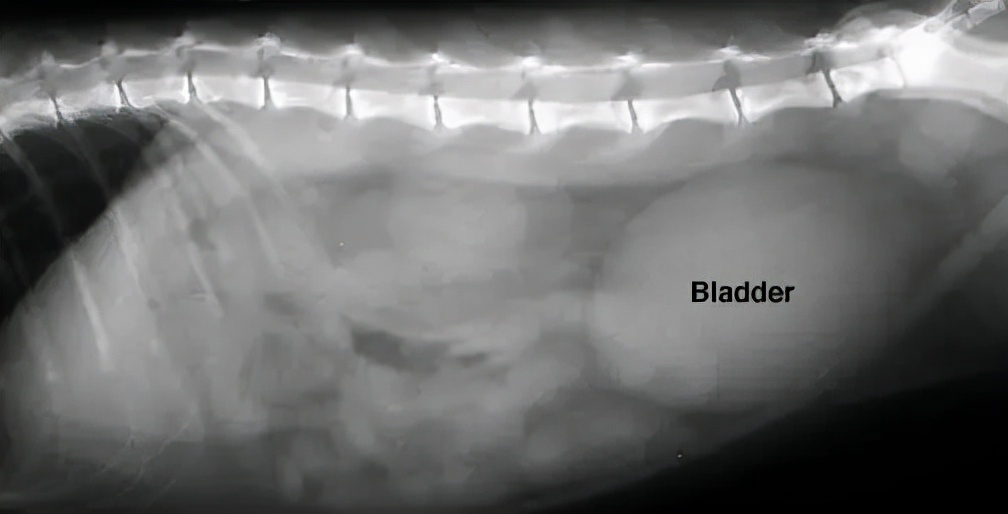

通常建议进行血液学检查(血常规、血液生化)和尿液检查,来帮助寻找尿道阻塞的原因,而X线和B超能帮我们判断是否有尿结石、尿结晶或尿道栓子。

↑图片右侧的的椭圆形影像是一个充盈的膀胱

针对小猫咪来说,最重要的是尽快恢复尿道通畅。